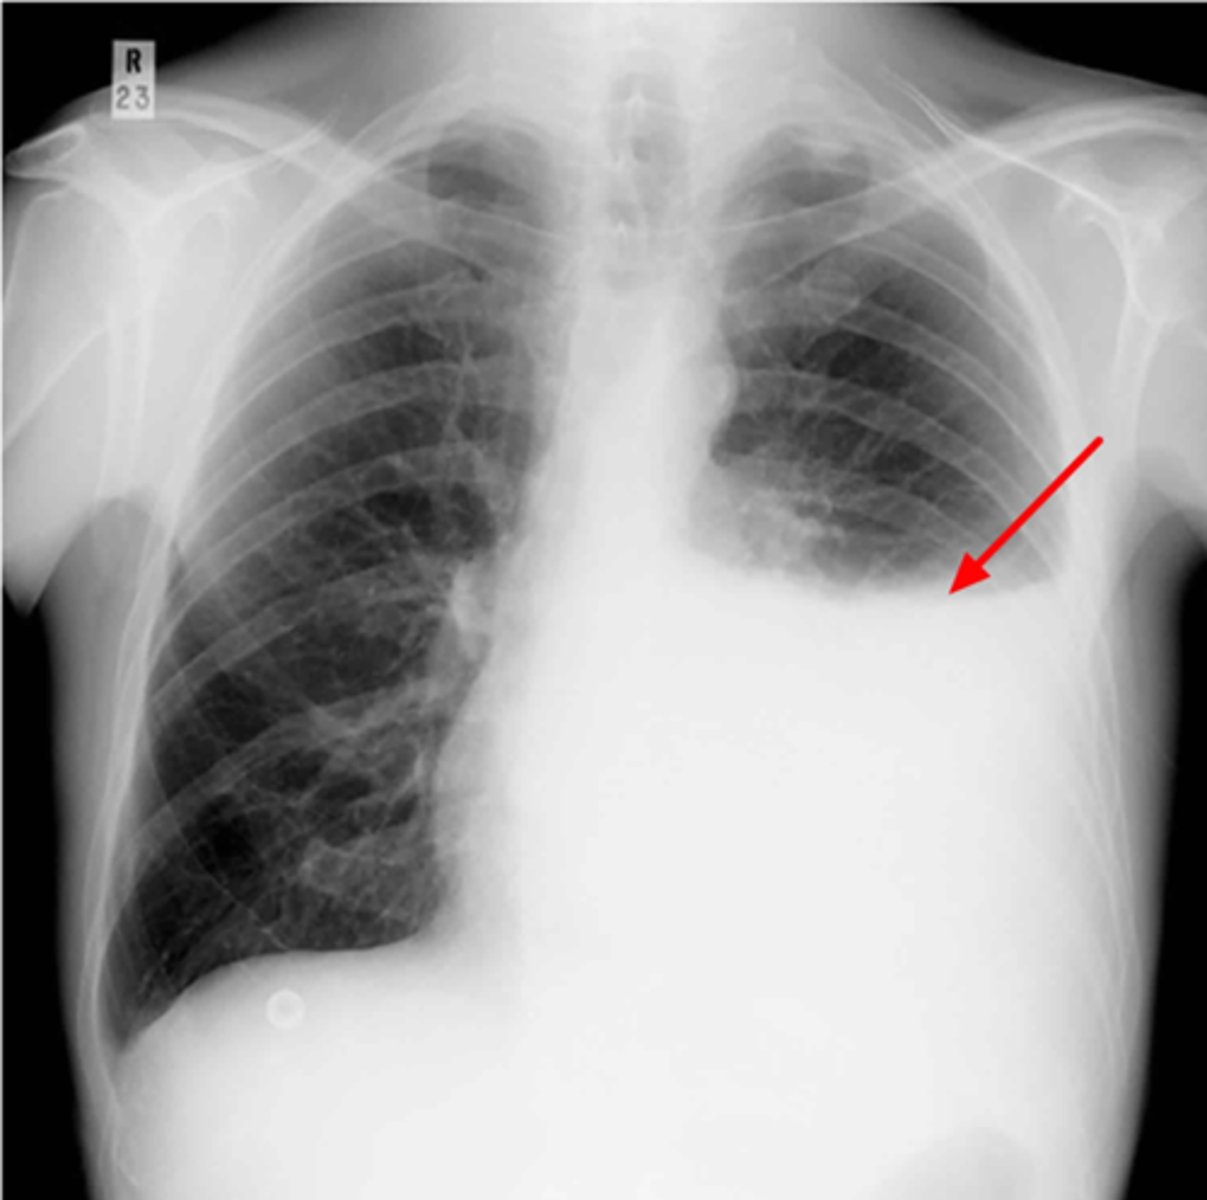

Left lung

Where is the abnormality located in the chest?

Atelectasis

What is the red arrow indicating?

Effusion

What is the likely interpretation?